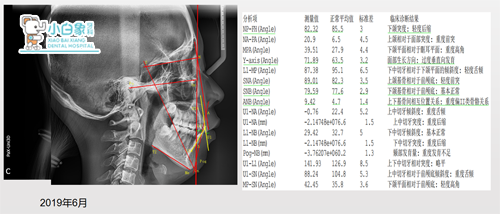

治疗前x线片

诊断

骨性二类

牙行一类

牙列拥挤

个别牙反合

牙龈炎